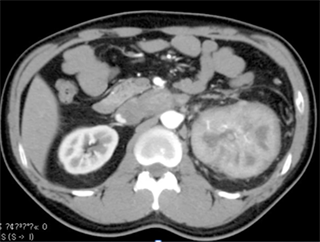

A 47-year-old man was referred to our institute with an enlarging left RCC. Computed tomography scanning revealed a large enhanced mass in the left kidney (Figure 1(a)) and local extension into the infrahepatic IVC (Figure 2) with pulmonary tumor embolism (Figure 3(a)). The embolism was located at the proximal portion of the right pulmonary artery, with no suspicious lesions in the left lung. As the mass of the RCC had been rapidly increasing in size for the past 2 months, early surgery was scheduled.

Figure 2. Computed tomography scan showing local extension of the left renal tumor into the infrahepatic inferior vena cava (white arrow heads).